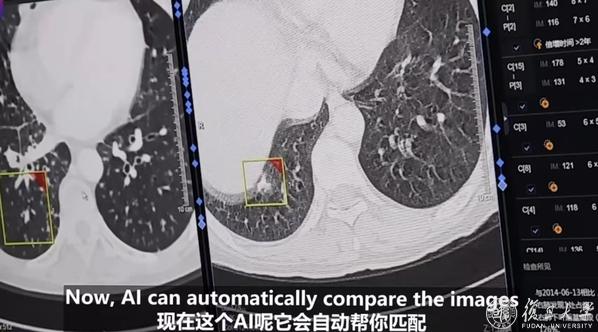

肺癌的早期发现至关重要,肿瘤医院放射诊断科在该领域借助AI技术取得新突破。放射诊断科主任顾雅佳介绍,AI在医学影像领域应用广泛,在肺癌筛查中,胸部CT检查的薄层扫描会产生大量图像,以往依靠医生人眼识别,不仅工作量大,还容易出现疏漏。

如今,AI能够不知疲倦地工作,快速准确地检出肺内结节,并对其性质作出初步判断,为医生提供参考,大大节省了诊断时间,提高了判断的准确性。放射诊断科医生王升平也表示,低剂量CT检查时,AI能凭借算法和模型,精准寻找可能的异常病灶,避免小病变的漏诊。

除了病灶检出,在肺癌患者的长期随访中,AI同样发挥着关键作用。它可以自动匹配患者前后的影像资料,进行精确测量比较,帮助医生直观地判断治疗效果,及时发现新病灶,为后续治疗方案的调整提供有力依据。